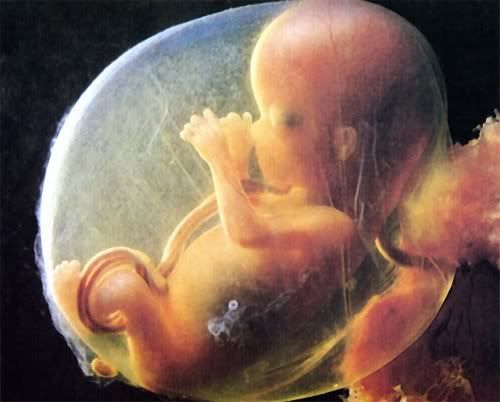

La gravidanza procede bene ed ormai siamo veramente agli sgoccioli. Girovagando per internet guardate cos'ho trovato....incredibile....è veramente il MIRACOLO DELLA VITA

La gravidanza procede bene ed ormai siamo veramente agli sgoccioli. Girovagando per internet guardate cos'ho trovato....incredibile....è veramente il MIRACOLO DELLA VITA